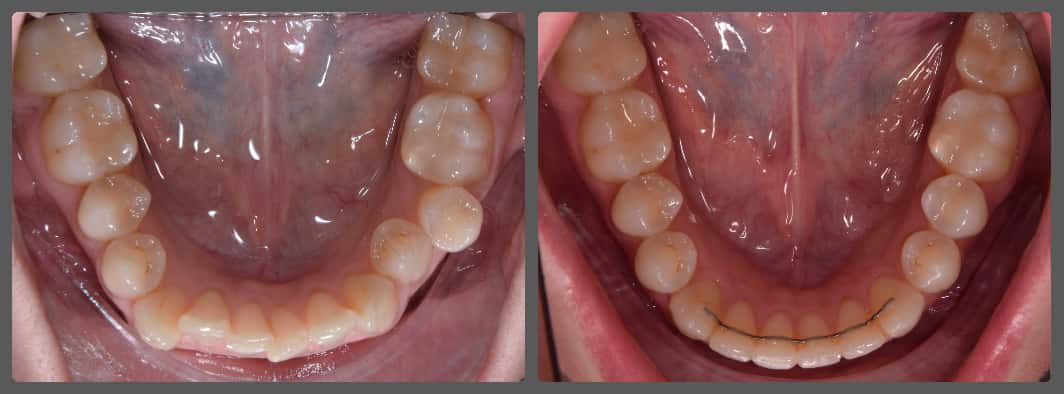

Zoli és szülei fogszabályozási konzultációra érkeztek hozzám alsó torlódása miatt. A közepes mértékű mélyharapáson túl nem diagnosztizáltam jelentős eltéréseket. A nyílirányú síkban tökéletes állcsontviszony volt látható, és a fogívek szélességével sem volt jelentős probléma. Alsó-felső Pitts21 fix önligírozó fogszabályozó készülékkel kezeltem Zolit. A harapást harapásemelők és intermaxilláris gumihúzás segítségével emeltük meg. A kezelés végén az alsó fogívre fix retainert helyeztem fel az elért eredmény megőrzésére. A teljes kezelés csupán 14 hónapig tartott!